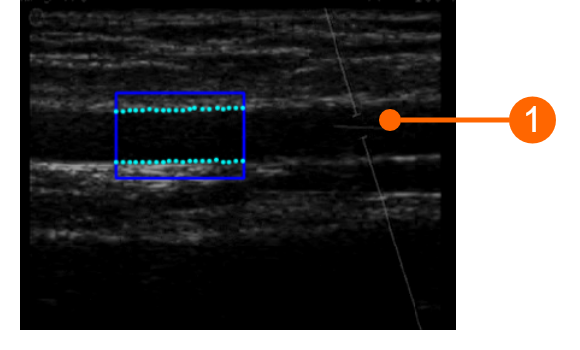

Example of brachial artery image

For FMD Studio we recommend an image depth of 2-3 cm. It is suggested also to choose a projection so that the vein is not visible (this normally appears immediately above the brachial artery). The algorithm for automatic tracking of the edges of the vessel could recognize the edge of the vein instead of the artery.

The angle between the Doppler beam and the vessel orientation should be ≤60 degrees. The sample volume should be as wide as possible but without encompassing the vessel walls and allowing for a slight margin for error in case of movement. Pay attention that the cursor of the doppler sample volume is not into the ROI where the diameter is computed. It is recommended that the sample volume is 5 - 15 mm apart from the ROI.

CAUTION: pay attention that nothing but the ultrasound image is into the ROI. Please note that the processing can be affected by annotations or any other graphical object that is superimposed to the image. In particular, pay attention that the cursor of the doppler sample volume is not into the ROI. |